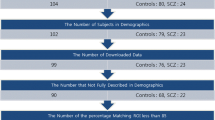

Functional magnetic resonance imaging (fMRI) is a fairly new technique that has the potential to characterize and classify brain disorders such as schizophrenia. It has the possibility of playing a crucial role in designing objective prognostic/diagnostic tools, but also presents numerous challenges to analysis and interpretation. Classification provides results for individual subjects, rather than results related to group differences. This is a more complicated endeavor that must be approached more carefully and efficient methods should be developed to draw generalized and valid conclusions out of high dimensional data with a limited number of subjects, especially for heterogeneous disorders whose pathophysiology is unknown. Numerous research efforts have been reported in the field using fMRI activation of schizophrenia patients and healthy controls. However, the results are usually not generalizable to larger data sets and require careful definition of the techniques used both in designing algorithms and reporting prediction accuracies. In this review paper, we survey a number of previous reports and also identify possible biases (cross-validation, class size, e.g.) in class comparison/prediction problems. Some suggestions to improve the effectiveness of the presentation of the prediction accuracy results are provided. We also present our own results using a projection pursuit algorithm followed by an application of independent component analysis proposed in an earlier study. We classify schizophrenia versus healthy controls using fMRI data of 155 subjects from two sites obtained during three different tasks. The results are compared in order to investigate the effectiveness of each task and differences between patients with schizophrenia and healthy controls are investigated.